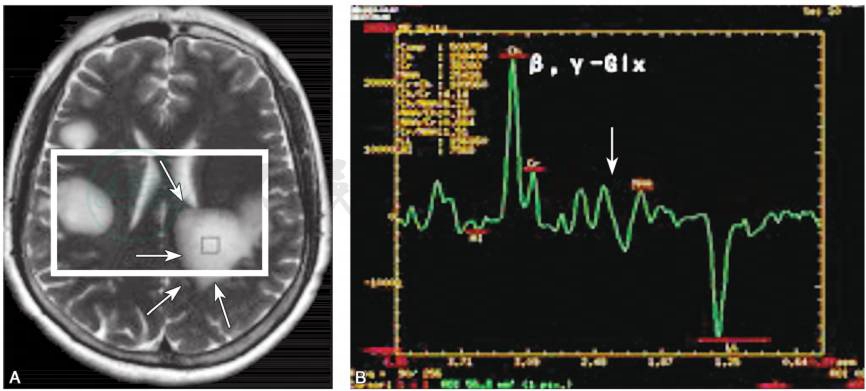

3)磁共振波谱(magnetic resonance spectroscopy,MRS):

可反映病变组织的代谢情况,对TIDD与脑胶质瘤与PCNSL的鉴别具有一定的临床价值。TIDD的MRS主要表现为胆碱(Cho)峰升高,N-乙酰天门冬氨酸(NAA)峰降低,多数还伴有一定程度乳酸(Lac)峰升高(图7)。

图7TIDD“云片状”病灶

A.双侧额叶皮质下云片状长T2异常信号,边缘呈短T2信号;B.1H-MRS显示,定位区域为左侧顶叶角回侧脑室旁病灶区(图3-12-24A),Cho峰显著升高,Cho/Cr=2.93,NAA 峰轻度降低,NAA/Cr=0.62,Lac峰显著升高(TE=144),β,γ-Glx峰升高

引自:神经病学:全2册.第3版.ISBN:978-7-117-31406-0.主编: